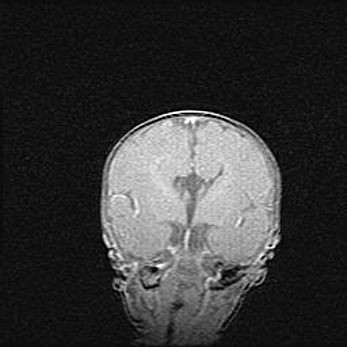

Наружная гидроцефалия с возможной атрофией височных областей.

Возраст: 28 дней

Вес: 3670 г

Пол: мужской

Окружность головы: 38 см

Срок гестации: 40 недель

Гидроцефалия головного мозга у новорожденных – это заболевание, которое характеризуется скоплением избыточного количества спинномозговой жидкости в желудочковой системе головного мозга в результате затруднения её перемещения от места выработки к месту поглощения в кровеносную систему или вследствие нарушения абсорбции. При открытой наружной форме гидроцефалии у новорожденных расширяются и переполняются субарахноидные пространства.

При нормотензивных  формах,  которые,  как  правило,  являются  следствием  перенесенных ишемических  повреждений  паренхимы  мозга,  возможно  сочетание микроцефалии  с нормотензивной гидроцефалией. В основе данных изменений лежит атрофия больших полушарий с преимущественной  локализацией  в  лобно-височных  областях.